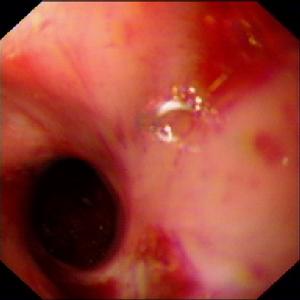

腐蝕性食管灼傷多為誤吞強酸或強鹼等化學腐蝕劑引起食管化學性灼傷。亦有因長期反流性食管炎、長期進食濃醋或長期服用酸性藥物(如強力黴素、四環素、阿司匹林等)引起食管化學性灼傷者,但較少見。

腐蝕性食管灼傷根據灼傷的病理程度,一般可分為I度、Ⅱ度、Ⅲ度灼傷:

①I度:食管黏膜表淺充血水腫,經過脫屑期以後7~8天而痊癒,不遺留瘢痕。

②Ⅱ度:灼傷累及食管肌層。在急性期組織充血、水腫、滲出,組織壞死脫落後形成潰瘍。3—6周內發生肉芽組織增生。以後纖維組織形成瘢痕而導致狹窄。

③Ⅲ度:食管全層及其周圍組織凝固壞死,可導致食管穿孔和縱隔炎。灼傷後病理過程大致可分為三個階段。